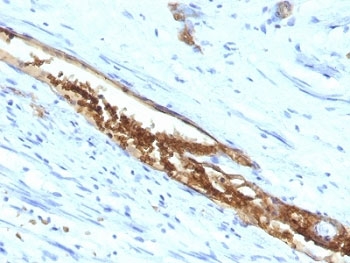

IHC: Formalin-fixed, paraffin-embedded human colon carcinoma stained with Blood Group Antigen A antibody (3-3A)

This mAb preferably reacts with determinants of chain A and H type 3 (Gal1-3GalNAc-R) and 4 (Gal1-3GalNAc-R), but not with type 1 and 2 chain structures. It is not reactive with immuno-dominant A trisaccharide. This mAb is applicable for tissue staining in tumor patients with blood groups A and AB. It shows a highly heterogeneous reactivity in human colon tumor tissue and adjacent mucosa. Blood-group antigens are generally defined as molecules formed by sequential addition of saccharides to the carbohydrate side chains of lipids and proteins detected on erythrocytes and certain epithelial cells. The A, B and H antigens are reported to undergo modulation during malignant cellular transformation. Blood group related antigens represent a group of carbohydrate determinants carried on both glycolipids and glycoproteins. They are usually mucin-type, and are detected on erythrocytes, certain epithelial cells, and in secretions of certain individuals. Sixteen genetically and biosynthetically distinct but inter-related specificities belong to this group of antigens, including A, B, H, Lewis A, Lewis B, Lewis X, Lewis Y, and precursor type 1 chain antigens.